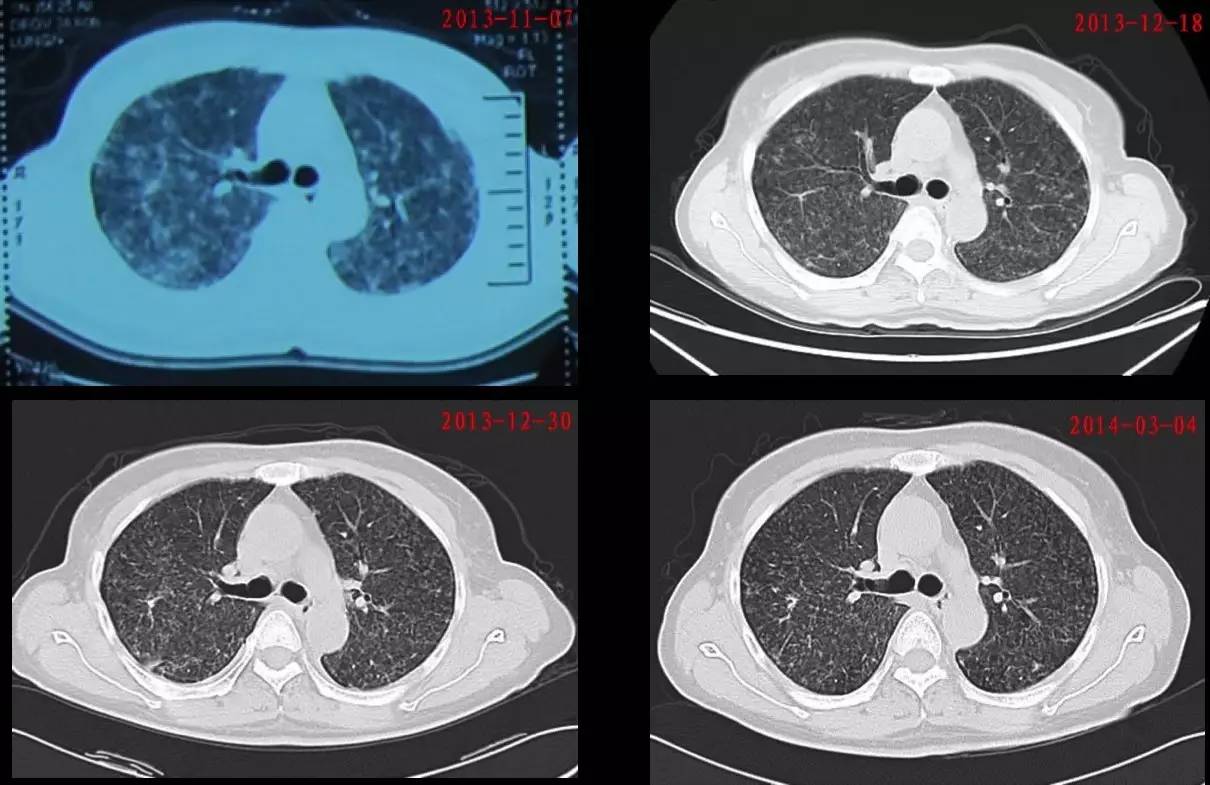

1. 胸部CT提示双肺病变较前吸收(图5)。

图 5:该患者治疗前后胸部CT对比